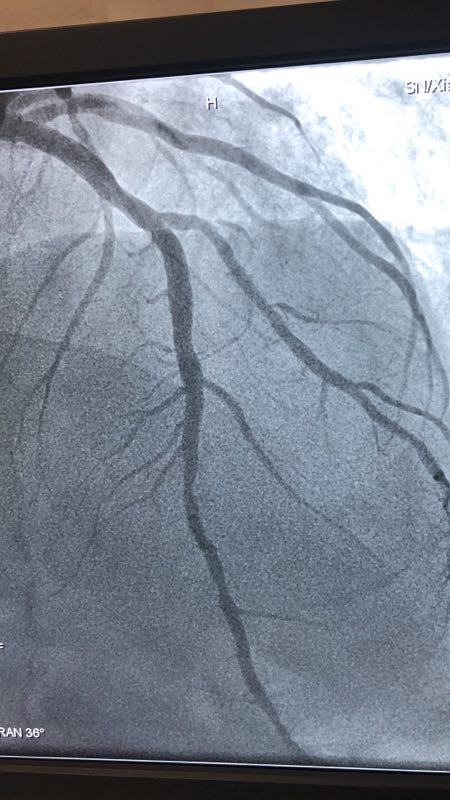

2018年12月27日下午,男同视频 CCU病区成功应用药物涂层球囊扩张术救治一名支架内再狭窄患者。

此例患者,男性,56岁,11年前因心绞痛在西京医院行冠状动脉造影检查后于D1对角支置入1枚支架治疗。术后患者口服“阿司匹林肠溶片、氯吡格雷、阿托伐他汀”等药物治疗1年后自行停药,并有长期大量吸烟史。2018年12月24日患者突发胸痛、胸闷,急来男同视频 就诊。急诊行冠状动脉造影检查提示D1对角支原支架内再狭窄70%-90%。急救中心主任张誉洋副主任医师考虑到第一对角支管径较小,于原支架内再次置入支架引起再狭窄的风险极大,遂建议应用药物涂层球囊扩张术治疗D1对角支原支架内狭窄。与患者充分沟通后,于12月27日行冠脉药物涂层球囊PTCA术治疗,造影显示血管开通情况良好,术后患者症状明显改善。

冠脉药物涂层球囊扩张术,由于不需置入外来物质,因此可以避免置入支架的很多缺陷。既达到“支架”扩张血管的目的,同时还能避免术后血管再狭窄,可谓一举两得。该技术可应用于小血管病变和不能耐受长期强化抗血栓治疗的患者,随着临床应用的增加可为更多患者带来福音。